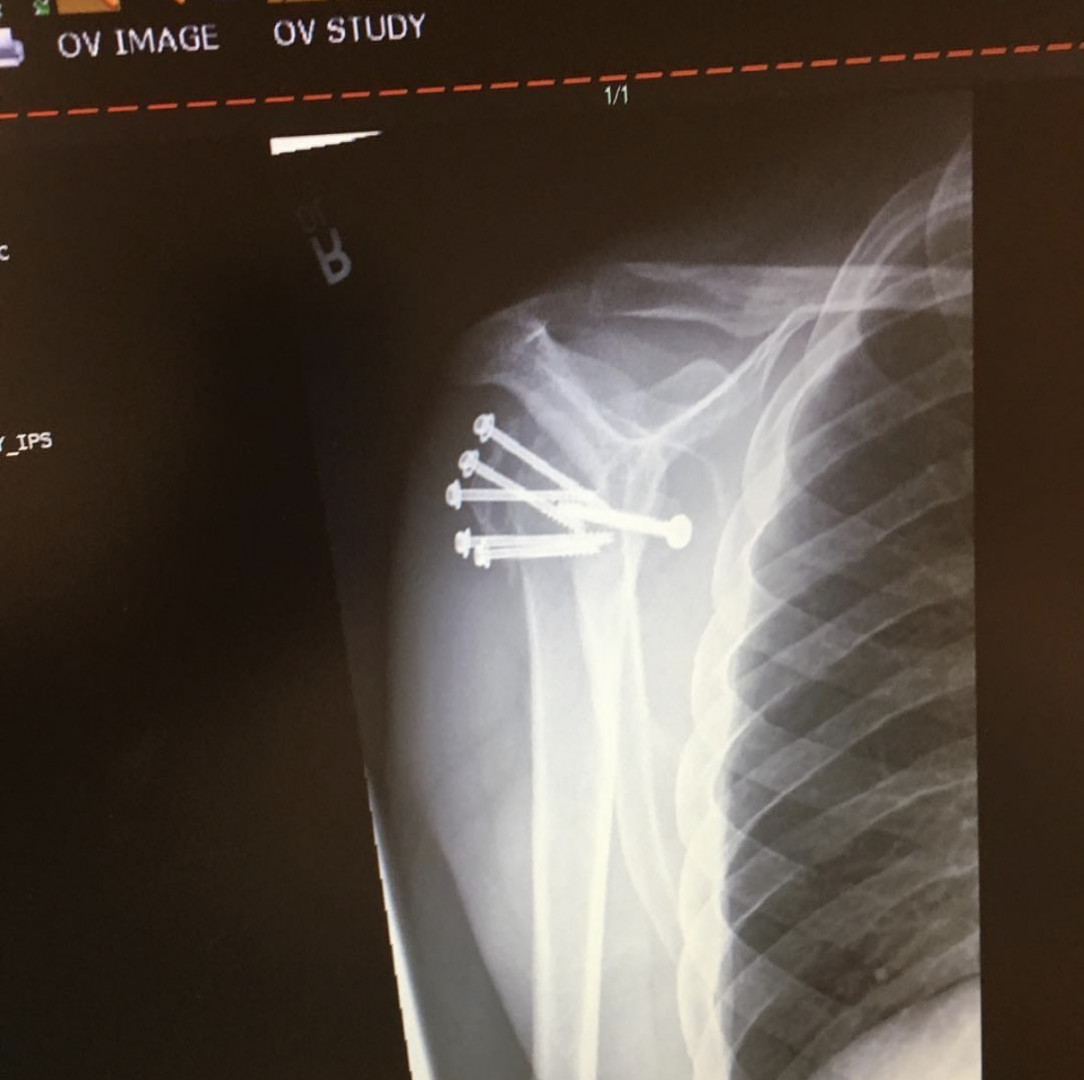

I do property management as a maintenance manager and have gotten in great shape since I had a shoulder reconstruction and hand surgery.